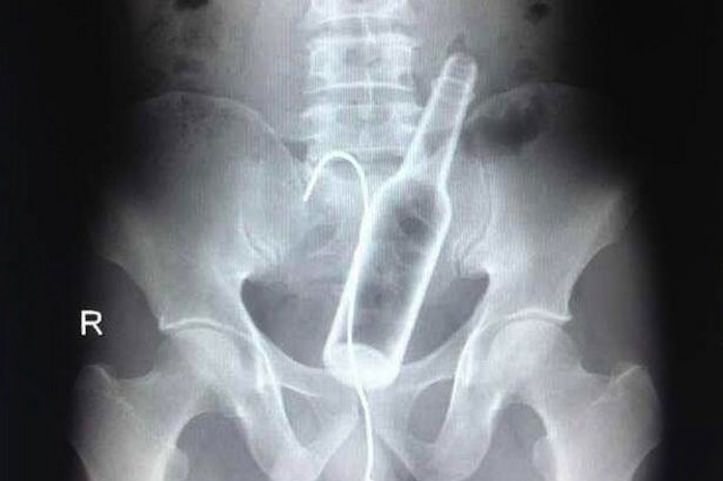

ゴリミーブログ 話題のネタ おもしろ画像 【意味不明】腹痛を訴えて病院に来た中国人男性、ガラス瓶を飲み込んでいたことが発覚! g.O.R.i 2014年01月12日 【意味不明】腹痛を訴えて病院に来た中国人男性、ガラス瓶を飲み込んでいたことが発覚! 僕のお腹が痛くなる時、原因は大抵ストレスか冷えすぎか食あたりのいずれか。多くの人もきっとそうだろう。 とある中国人男性はある日腹痛を訴え病院に行ってきた結果、なんとガラス瓶を飲み込んでいたことが明らかになった!そんなことあり得るのか?! 自分で取り出そうとした使ったワイヤーも飲み込んでしまった そもそもガラス瓶をどのような状況で飲み込んでしまったのか理解に苦しむが、男性のお腹の中に見つかったのは瓶だけではない。実は飲み込んでしまった直後、どうにかして瓶を抜き出そうとパニックのあまり鋼のワイヤーを使って瓶を引っ掛けようとしたようだが、結局それも飲み込んでしまったようだ。アホか。 その時のX線写真が以下。見ての通り、ハッキリとガラス瓶とワイヤーが写っていることが分かる。 それにしてもなぜビール瓶を飲み込むことになったのか。酔っ払って間違えて飲み込むとはさすがに考えられない。では何が起きたのか。 僕が勝手に想像するに、友人数名と飲んでいた時にテレビで剣を飲み込むマジックを見て、その場のノリで「俺だってビール瓶なら飲み込めるぜ!」と言ってやったものの、取り返しの付かないことになってしまった、という状況。アホか。(2回目) チャイニーズ・カルチャーはなかなか不思議ですなあ。 (via Gawker)